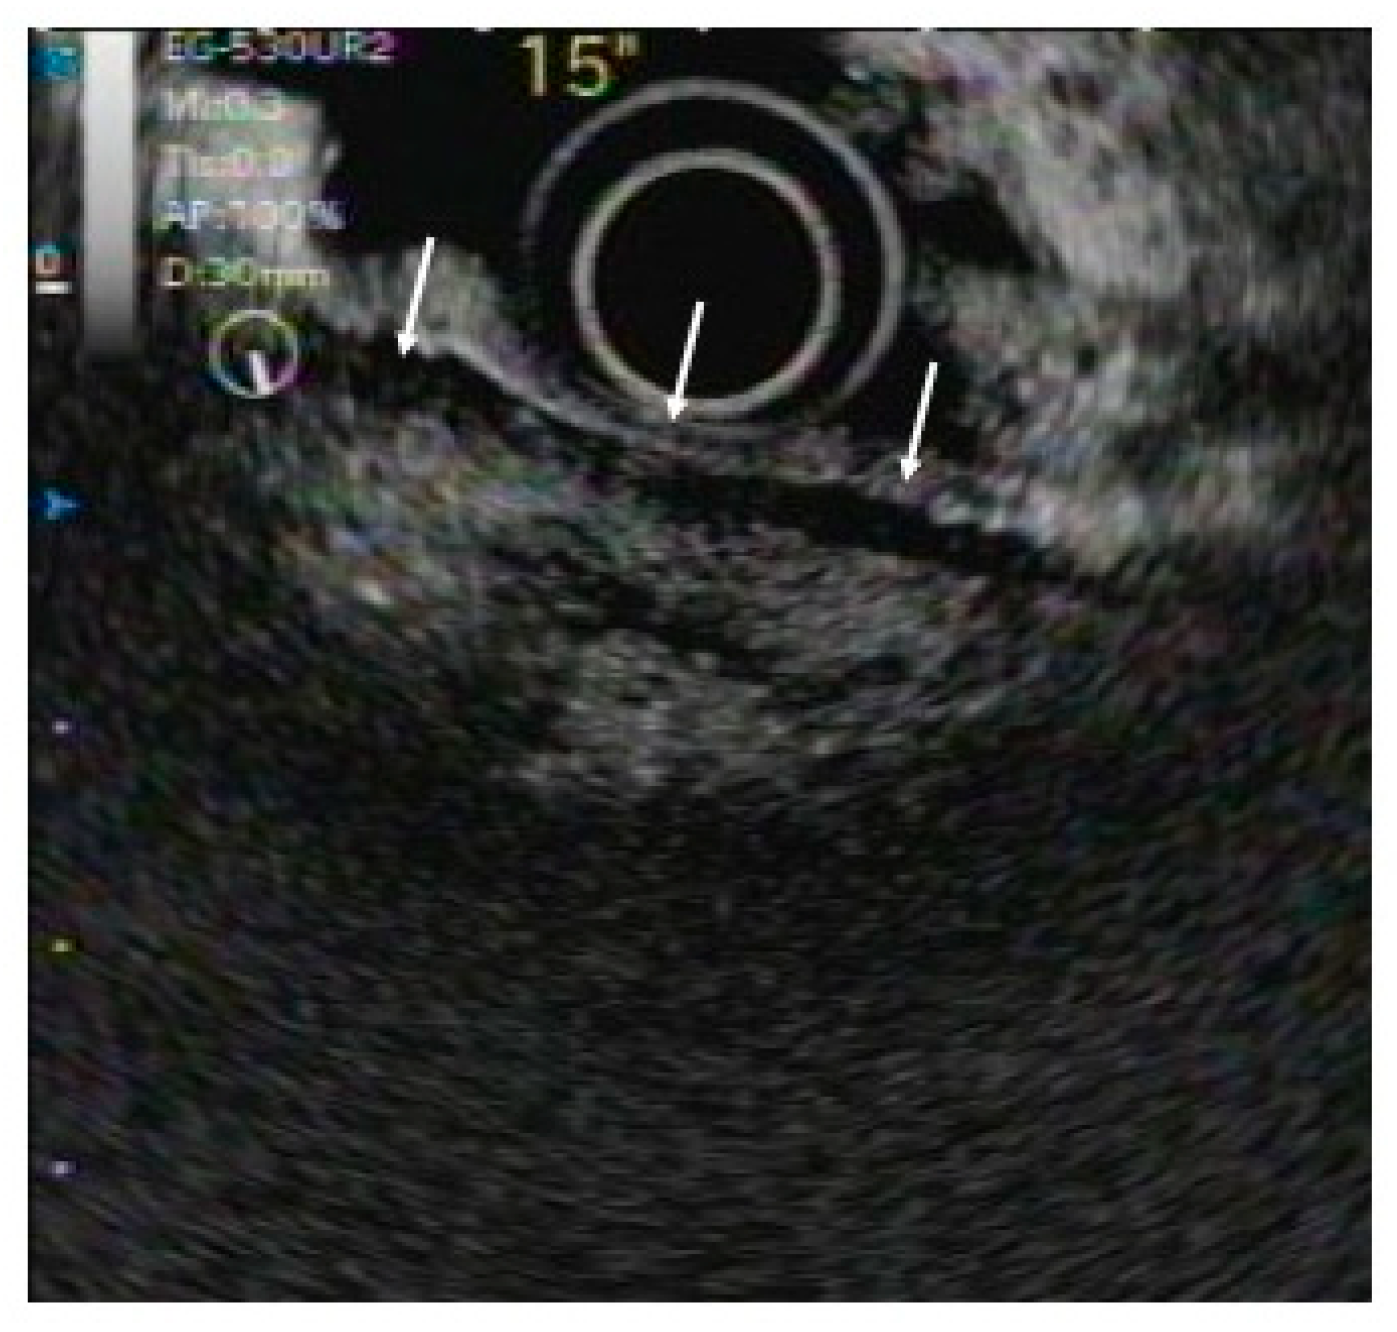

3.2. IDUS

- Naitoh, I.; Nakazawa, T.; Ohara, H.; Ando, T.; Hayashi, K.; Tanaka, H.; Okumura, F.; Takahashi, S.; Joh, T. Endoscopic transpapillary intraductal ultrasonography and biopsy in the diagnosis of IgG4-related sclerosing cholangitis. J. Gastroenterol. 2009, 44, 1147–1155. [Google Scholar] [CrossRef]